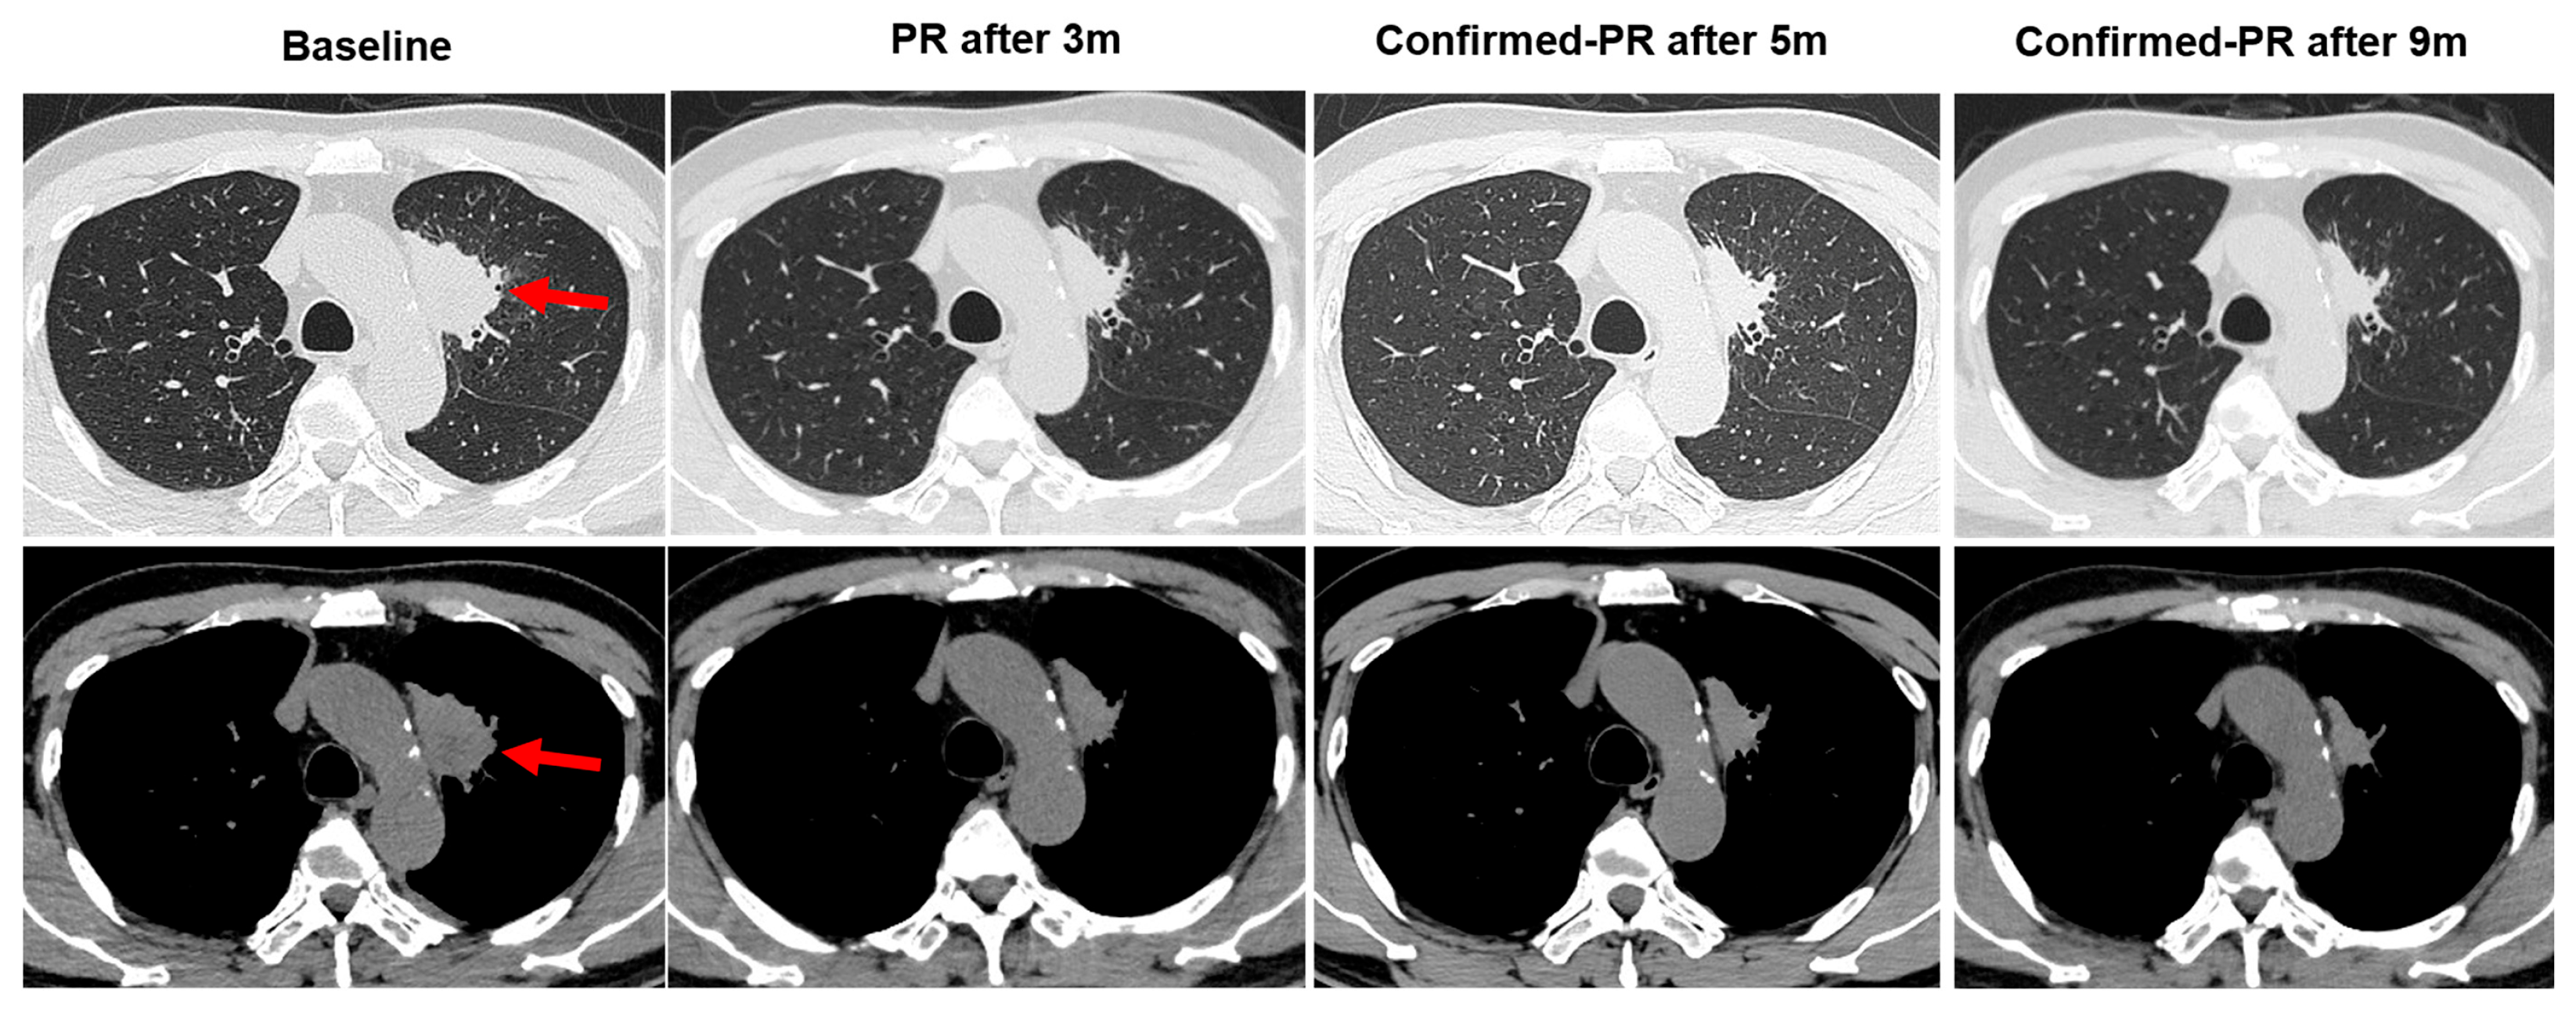

3.1. Case Description